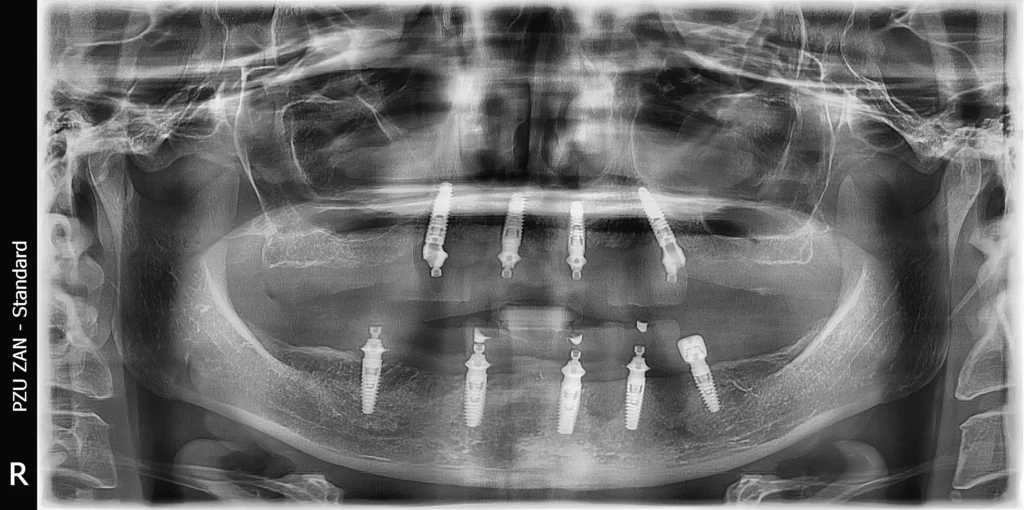

After the examination and all the analysis, the therapy plan consisted of a full mouth reconstruction with dental implants.  All the teeth were removed and the implants were placed immediately. The patient was provided with temporary teeth during the healing period.

After 6 months of osseointegration of the dental implants, we provided a new beautiful smile with a hybrid construction, zirconia on a titanium bar.